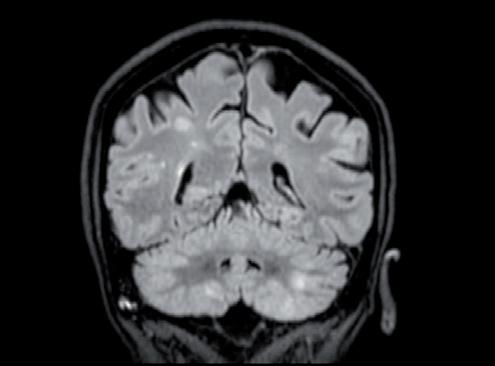

La paziente ha pertanto avviato una seconda linea di trattamento con T-DXd, ottenendo una progressiva riduzione delle lesioni meningee note ai successivi controlli mediante RM, fino ad arrivare a una situazione di stabilità che si mantiene tuttora a 24 mesi dall’avvio del trattamento (figura 1).

Figura 1. Immagini RM prima dell’avvio del trattamento e dopo 6 mesi.